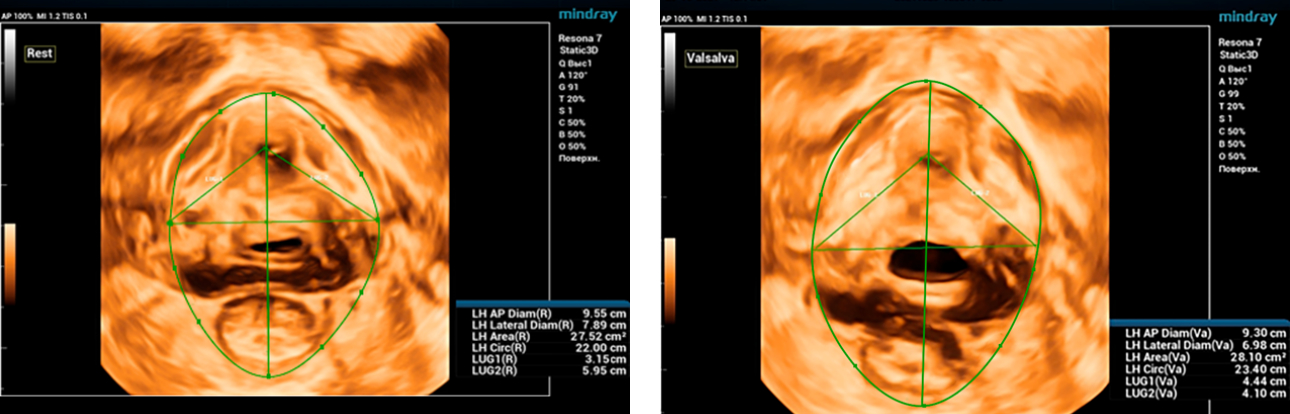

Endocavity ?? ?? ?? ???(DE10-3WU, Resona 7, Mindray)? ??? ??? ???? ?? ?? ????(Levator ani nuscle)? ??? ???. ???? ?? ??? 3~4mm? ????, ???(levator hiatus) ?? ?? - 6.13cm, LUG1(??? m ??? ??. Bulbocavernosus) ŌĆō 2.95cm ? LUG2 ŌĆō 3.15cm(?? 2.5cm ??)

??????? ??? ?? ? ??? ??? ??? ?????, ?? ??(pelvic floor) ??? ??? ?? ??(??? ?/?? ??)? ??? ???. ? ?? ???? PVA, RVA ? PUA ?? 20┬░ ???? ?????. ? ?? ???? PVA ŌĆō 134o, RVA ŌĆō 82o ? PUA ŌĆō 119o.

?? ? ???????? ?? ?? ??? ??? ???? ???? ?? ?? ??? ????. ????? ?????? ???? CUDI(??? ???? ??) ? ??? ??? ???? ? ??? ??? ? ?? ???, CUDI, ???(pessary)? ??? ?? ???(???? ??? ???? ? ? 7? ??). ?? ??? 3D ??? ? ?? ??? ??? ??? ?? ??? ?? ???? ??? ?? ?? ??? ????? ???? ?? ??? ??? ??? ????.